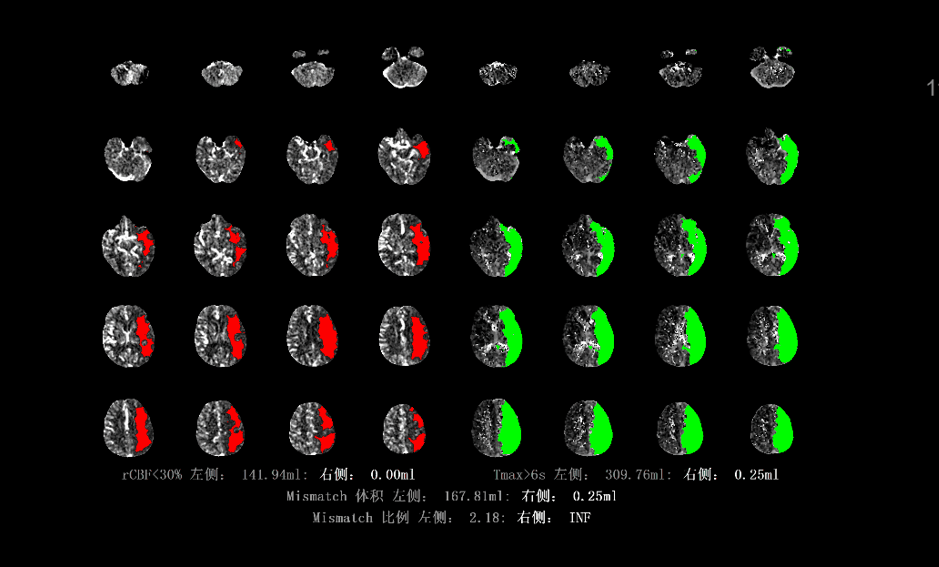

东软医疗NBC脑缺血图像辅助评估软件,是与首都医科大学宣武医院互联网医疗诊治技术国家工程实验室合作研发而成,可提供包含CBV,CBF,MTT,TTP,Tmax 5种参数的灌注图谱,同时还可自动计算缺血半暗带和核心梗死区的比值和体积,进而辅助临床医生快速进行救治决策,为最终提高评估精准度与救治效率奠定基础。

NBC软件可以快速评估缺血半暗带和核心梗死区,给临床医生快速启动血管内治疗、挽救患者生命提供了更多科学依据,有极大的临床推广价值。